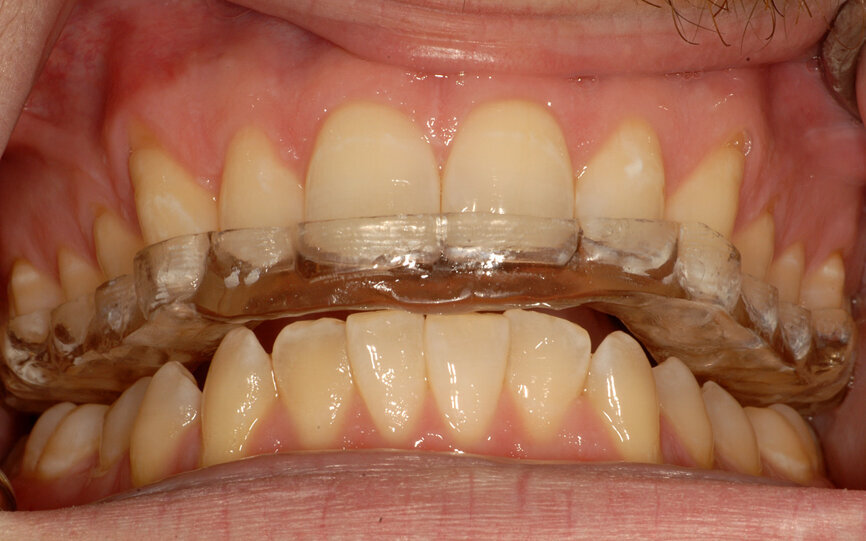

Fig. 21: Composite resin device at the desired vertical dimension of occlusion stabilises the mandible in centric relation.

- Create a composite resin device (stop) on an anterior tooth (Fig. 21) at an approximate VDO to allow restorative space.

- Ask the patient to move the mandible forward and backwards two to three times. That will relax the lateral pterygoid muscles and allow the elevator muscles to position the condyles in a physiological position on the eminences.

- Adjust the composite resin device, using articulating paper, for a smooth mandibular movement. Also, adjust the height until the desired VDO is reached—evaluate the anterior space first, then the posterior space and then adjust the prepared teeth if needed to gain the appropriate restorative space.

- After the adjustments, ask the patient to maintain the backward position. That can be considered CR.